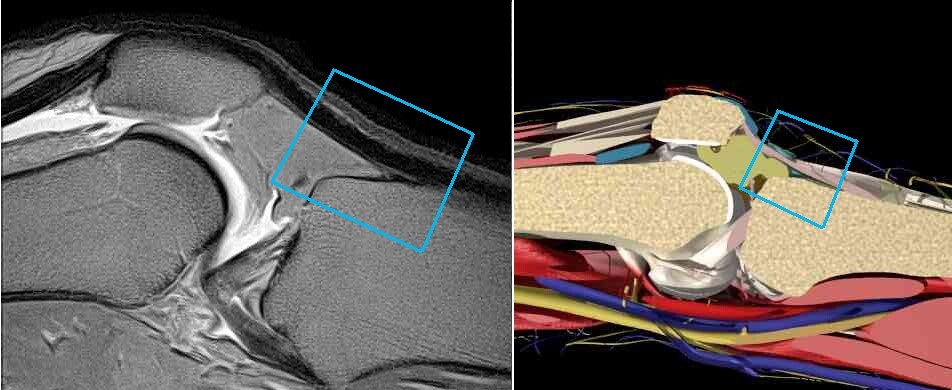

Knee Infrapatellar Tendon MRI Equivalent Graphic